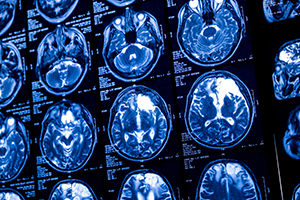

脳疾患センターでは急性期脳卒中の診断に必要な画像検査である頭部CT、MRI、脳血管造影検査(カテーテル検査)は24時間365日実施可能です。

専門医が24時間常駐しているので診断・治療を速やかに行えます。